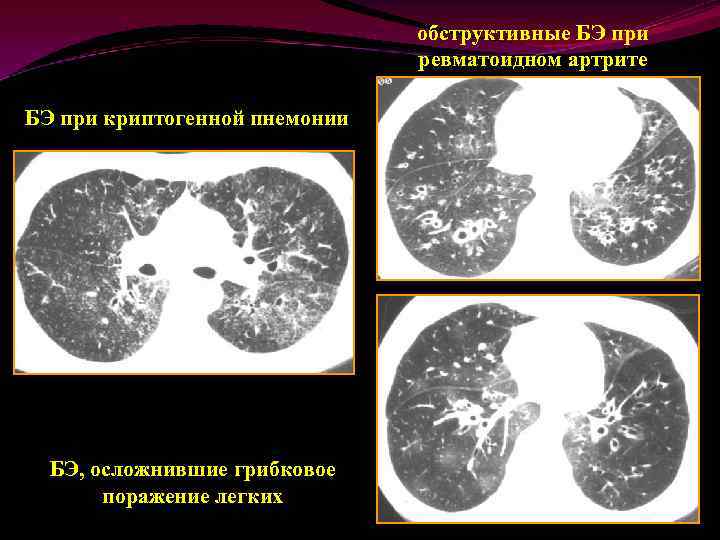

обструктивные БЭ при ревматоидном артрите БЭ при криптогенной пнемонии БЭ, осложнившие грибковое поражение легких